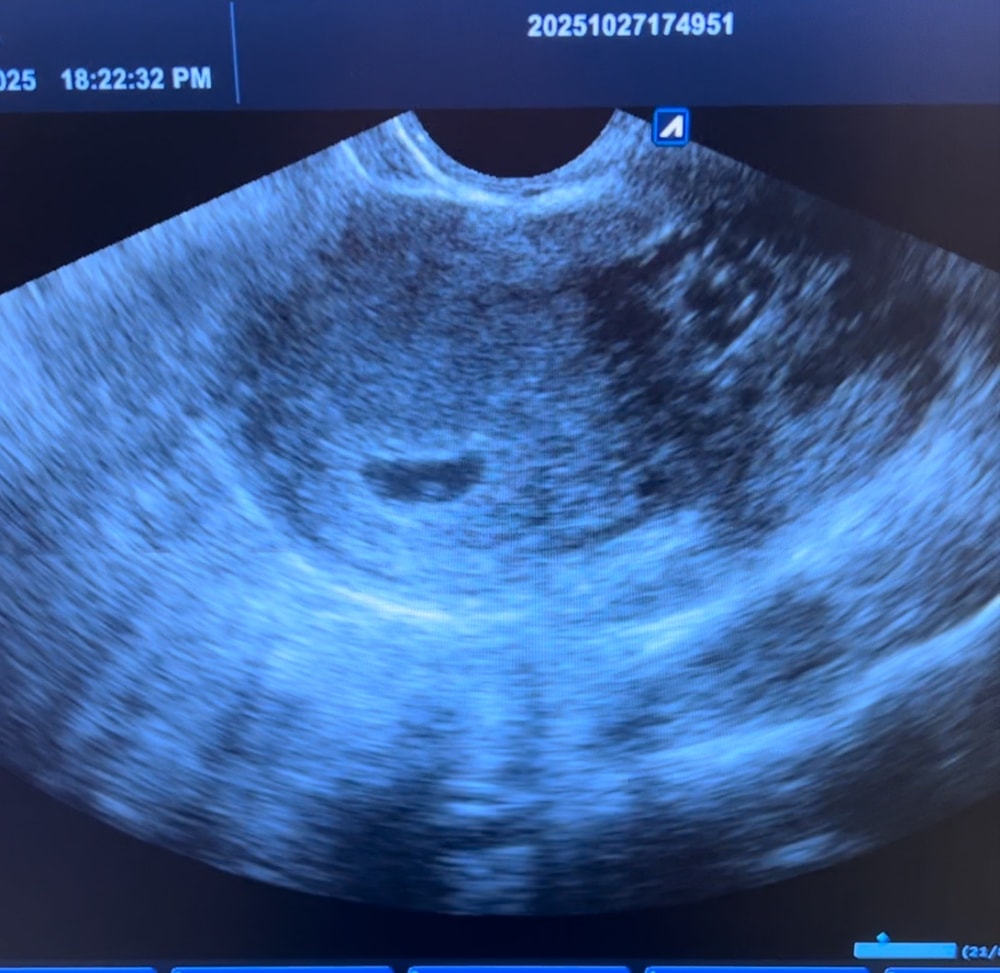

Девочки, расскажите, были ли тут у кого-то ситуации похожие с моей. У меня очень нерегулярный цикл, были кисты часто, цикл сильно удлинен. По УЗИ ставят беременность 6 недель и 1 день. По месячным 7 недель и 3 дня. Не видят эмбрион. ПЯ неделю назад было 13 мм, сегодня 32мм. Хгч растёт, (удваивается каждые 2-3 дня) (было 19000 стало 33000). По самоч